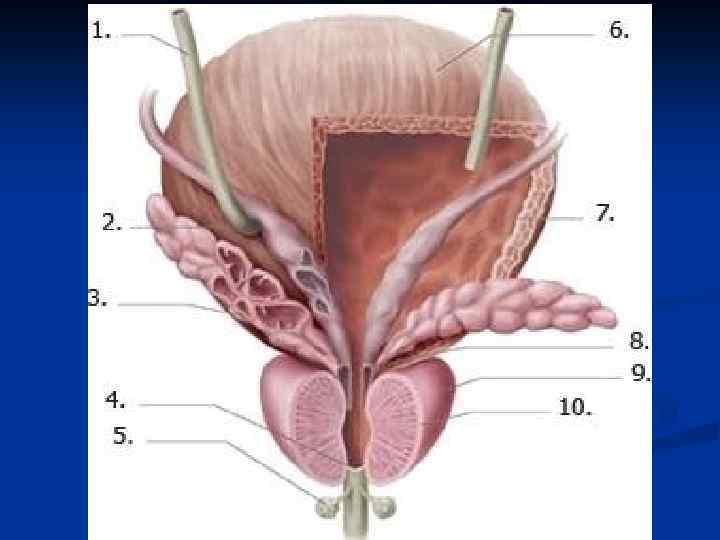

Путь выведения спермы: 1. Извитые семенные канальцы (700 -900) 2. Прямые семенные канальцы (250 -300) 3. Сеть яичка 4. Выносящие канальцы яичка (12 -15) 5. Проток придатка яичка 6. Семявыносящий проток (4 части – яичковая, канатиковая, паховая и тазовая) 7. Ампула семявыносящего протока + выделительный проток семенного пузырька 8. Семявыбрасывающий проток 9. Мужская уретра

Путь выведения спермы: 1. Извитые семенные канальцы (700 -900) 2. Прямые семенные канальцы (250 -300) 3. Сеть яичка 4. Выносящие канальцы яичка (12 -15) 5. Проток придатка яичка 6. Семявыносящий проток (4 части – яичковая, канатиковая, паховая и тазовая) 7. Ампула семявыносящего протока + выделительный проток семенного пузырька 8. Семявыбрасывающий проток 9. Мужская уретра

1. 2. 3. 4. 5. 6. 7. 8. 9. Путь выведения спермы: Извитые семенные канальцы (700 -900) Прямые семенные канальцы (250 -300) Сеть яичка Выносящие канальцы яичка (12 -15) Проток придатка яичка Семявыносящий проток (4 части – яичковая, канатиковая, паховая и тазовая) Ампула семявыносящего протока + выделительный проток семенного пузырька Семявыбрасывающий проток Мужская уретра

1. 2. 3. 4. 5. 6. 7. 8. 9. Путь выведения спермы: Извитые семенные канальцы (700 -900) Прямые семенные канальцы (250 -300) Сеть яичка Выносящие канальцы яичка (12 -15) Проток придатка яичка Семявыносящий проток (4 части – яичковая, канатиковая, паховая и тазовая) Ампула семявыносящего протока + выделительный проток семенного пузырька Семявыбрасывающий проток Мужская уретра